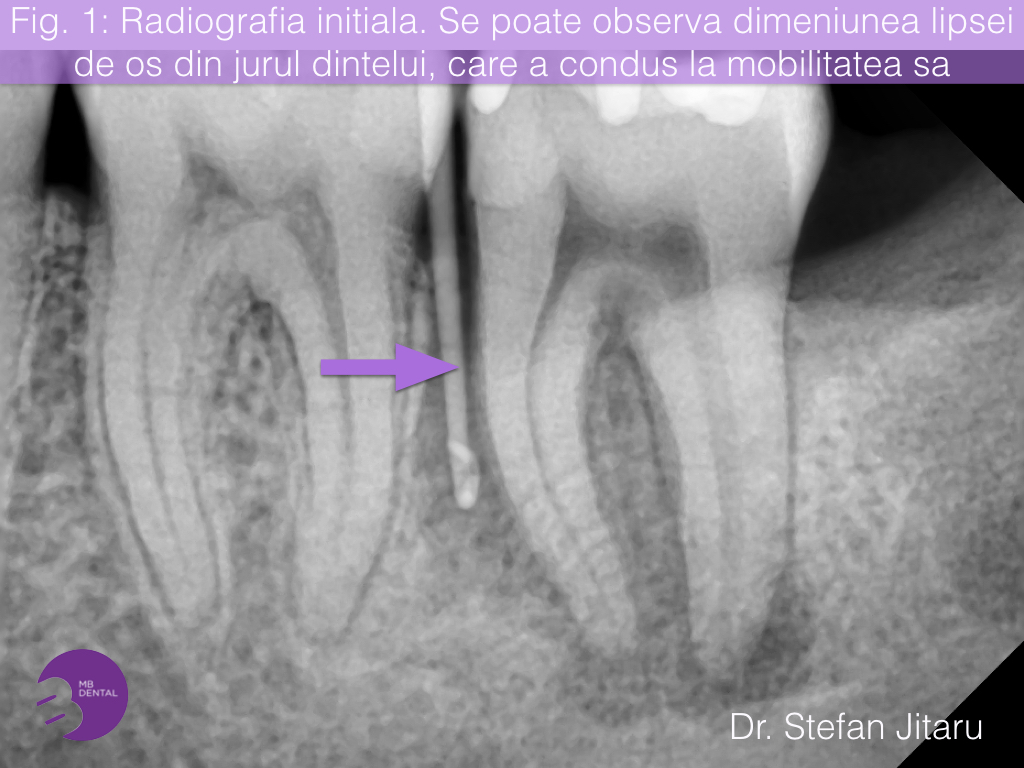

Pentru a completa informatiile necesare unui diagnostic, am realizat o radiografie digitala unidentara pe care am putut observa ca exista o zona extinsa de lipsa osoasa care inconjoara radacinile dar si zona marginala coroanei dintelui. Pe radiografie puteti observa cum tija indicata de sageata a putut fi introdusa pe langa dinte dinte in zona in care osul lipsea fiind deja resorbit (Fig. 1)